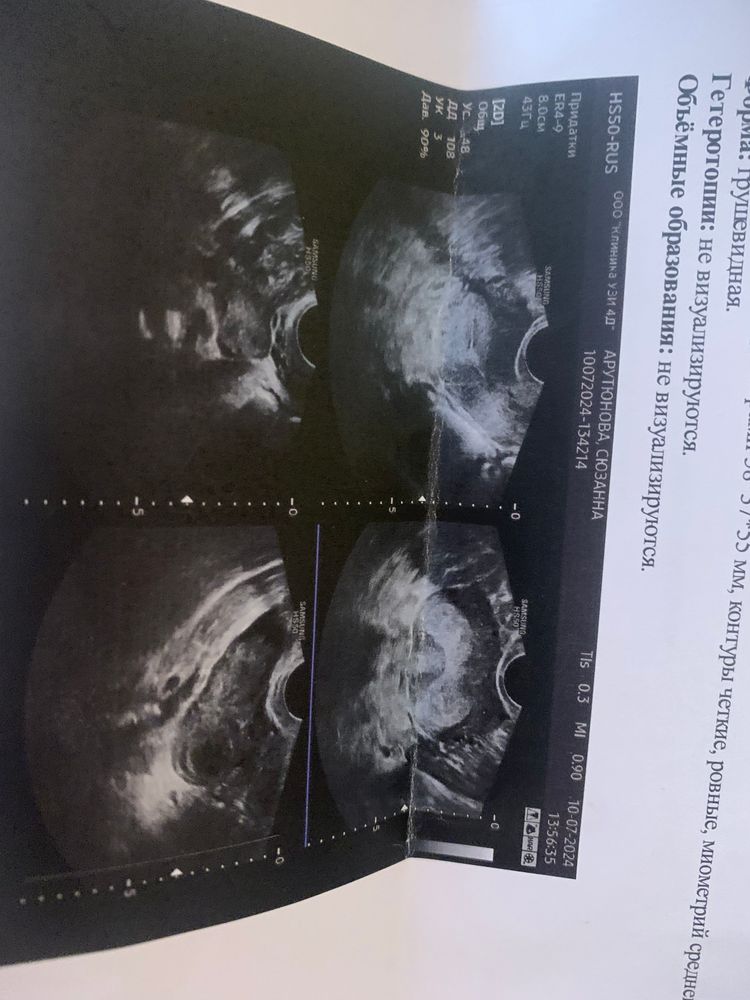

Желтое тело в яичнике левом, и хгч за тысячу Про внематочную ничего не сказали?

Karmilla, она сказала что плодное яйцо четко не визуализируется

В левом яичнике была овуляция, эндометрий не вижу(или не увидела) размер. Через дней 10 сделайте тест

Zzzzzz, ну вот ЖТ признак случившейся овуляции (значит беременность не исключена), ХГЧ тому подтверждение. Пересдать ХГЧ, как рекомендуется, чтобы исключить внематочную. Потому что обычно от 1000/2000 единиц уже на УЗИ обычно видят